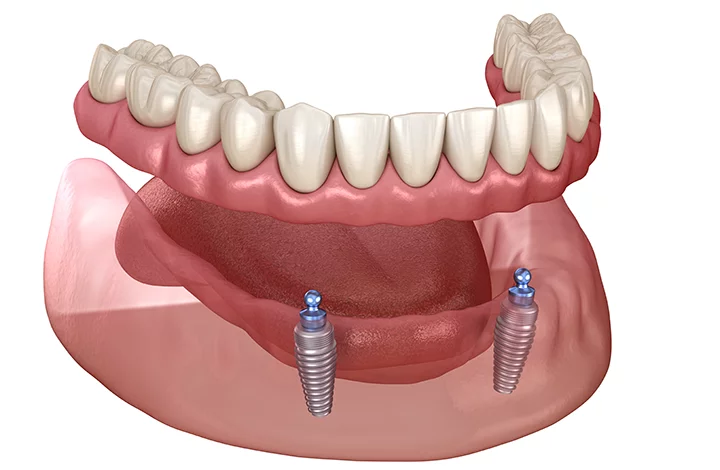

総入れ歯に不安のある方へ

インプラントオーバーデンチャー

インプラントオーバーデンチャーは、2~4本のインプラントを外科手術により顎の骨に埋め込み、これによって入れ歯をしっかりと固定する治療法です。この方法では、特殊な部品であるロケーターを使用し、インプラントと入れ歯を連結します。そのため、「アタッチメント義歯」とも呼ばれています。

この治療法の特長は、入れ歯が顎の骨に確実に固定されることにあります。これにより、入れ歯でも硬いものを噛めるようになったり、食事や会話の際に入れ歯がずれたり、外れたりする心配がなくなります。

インプラントオーバーデンチャーは、2~4本のインプラントを外科手術により顎の骨に埋め込み、これによって入れ歯をしっかりと固定する治療法です。この方法では、特殊な部品であるロケーターを使用し、インプラントと入れ歯を連結します。そのため、「アタッチメント義歯」とも呼ばれています。

この治療法の特長は、入れ歯が顎の骨に確実に固定されることにあります。これにより、入れ歯でも硬いものを噛めるようになったり、食事や会話の際に入れ歯がずれたり、外れたりする心配がなくなります。

また通常のインプラント治療と比較して大幅に費用を抑えることができるのも利点の一つです。